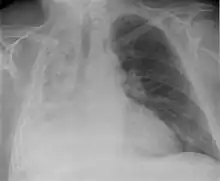

| Left tension pneumothorax with a large, well-demarcated area devoid of lung markings with tracheal deviation and movement of the heart away from the affected side. |

Tension pneumothorax

Tension pneumothorax is an emergent condition in which air gets trapped in the space between the chest wall and the lung. This space is referred to as the pleural space. Because air can't escape from this space, the air pocket grows larger and larger, resulting in the lung collapse closest to the pneumothorax. Forces are transmitted to the mediastinum and effectively "push" the mediastinal structures to the opposite side of the chest.[5]